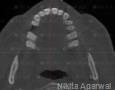

CBCT :

Yes

Pictures

Baseline